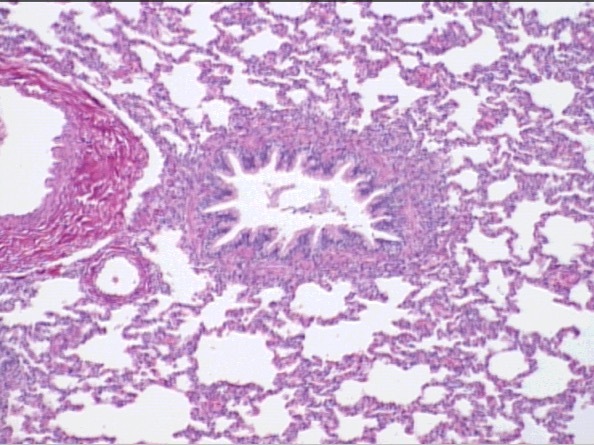

lung

bronchus

vessel

c/s bronchus

(look for hyaline cartilage)

bronchiole

bronchi

terminal bronchiole

note epithelial changes

simple columnar –> cuboidal

respiratory bronchiole

alveolar ducts

alveolar sac

alveolar duct